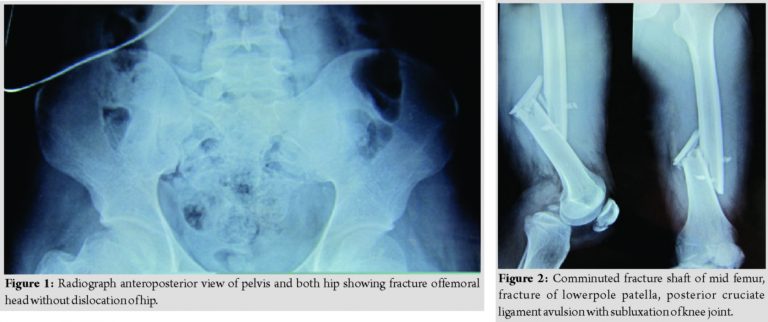

Radiographs done after primary resuscitation as per the standard protocol of advanced trauma life support. Radiographs revealed a fracture at the femoral head (Fig. 1), comminuted fracture Shaft of the mid femur, fracture of lower pole patella, posterior cruciate ligament avulsion with subluxation of the knee joint (Fig. 2), fracture talus, and fracture calcaneus (Fig. 3). There was no dislocation of the hip. Emergent ankle debridement was performed with stabilization of knee by upper tibial pin traction. A computed tomography scan of the right hip joint was done, which was suggestive of the femoral head fracture without dislocation or acetabular fracture (Fig. 4).

Femoral head fixation was performed after the fixation of fracture shaft femur by safe surgical dislocation of the hip approach. Intraoperative comminuted fracture of the femoral head(modified Pipkins type A-V) with avulsion of cartilage was found [5] (Fig. 5). The femoral head was approached by the method of safe surgical dislocation of the hip and fixation done with Herbert screws (Fig. 6).